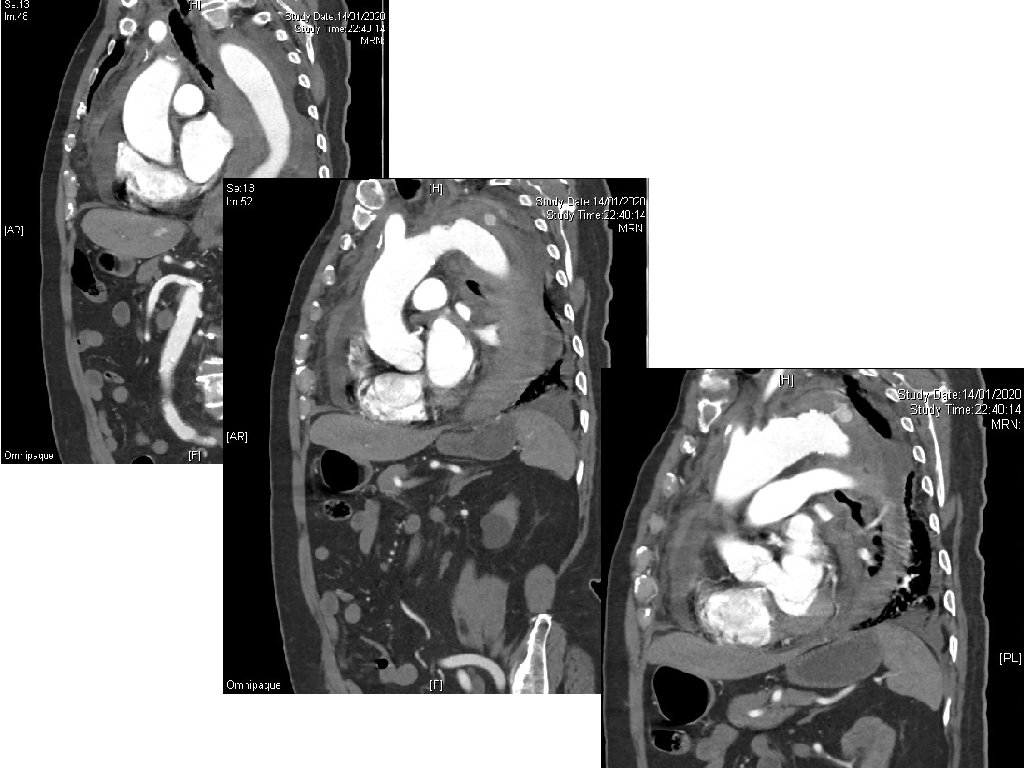

Case 3 • A 90 year-old man presented with sudden onset of back and chest pain. • His BP was 87/58, pulse 68/min. • A CXR was done.

Case 3 - Questions 1. Name three CXR abnormalities. 2. Name two useful bedside investigations and what to look for. 3. Name two most significant CT findings? 4. What is the diagnosis?